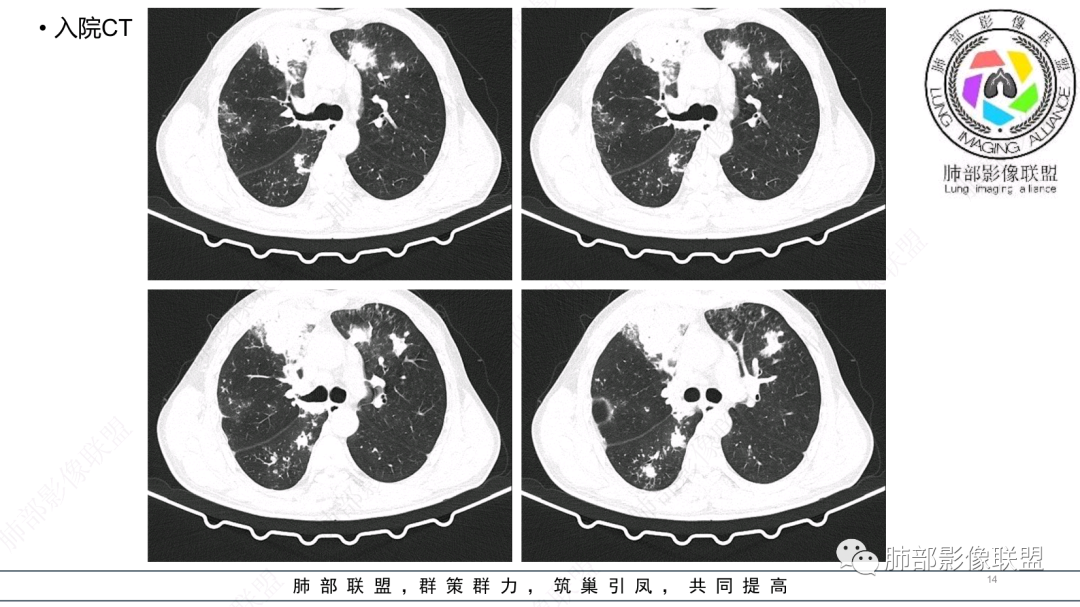

中老年男性,发病一周,发热,炎症指标明显增高,双肺支气管扩张基础,双肺可见多发结节、斑片状、团块状密度增高,边缘尚清。病灶分布与支气管关系密切,考虑支扩合并感染,铜绿,NTM、奴卡、曲霉等,环卫工人,可能接触腐败物较多,考虑曲霉可能大,鉴别奴卡。

中老年男性,发病一周,发热,炎性指标高,职业环卫工人,两肺弥漫分布肉芽肿结节病变,以胸膜下及支气管血管束分布为主,两肺多发支气管扩张,奴卡,结核,曲霉。

男性,56岁,清洁工,临床表现咳嗽咳痰发热。胸部影像:两肺散在斑片、结节及实变影,大部分沿气道分布,以下肺为著并伴发多发支气管扩张及囊腔影,实验室检查白细胞增高,考虑感染性病变,曲霉、铜绿及NTM。

56岁,工作性质:环卫工人。主诉:咳、痰、喘、发病一周。急性起病(或者慢病+AE),呼吸道感染症状。化验指标白细胞、中性、CRP明显升高。影像学显示多灶性,有柱状支扩,囊状支扩等结构肺病,责任细菌主要考虑铜绿假单胞菌,不排除合并其他细菌以阴杆为主;存在树芽影,发热,炎症沿支气管束分布,是否合并TB?真菌?;树芽伴发热支原体感染也要需要考虑进去;全肺多灶性炎症,部分病灶周围有晕,右上叶疑似反晕,内部疑似有丝,右下肺考虑存在粘液栓,加之环卫工工作性质,考虑霉菌,主要考虑曲霉。

两肺支扩,两肺沿支气管分布多发结节、树芽及团块,边缘模糊,部分支气管管壁增厚,考虑气道侵袭性曲霉菌,鉴别铜绿、奴卡、结核。